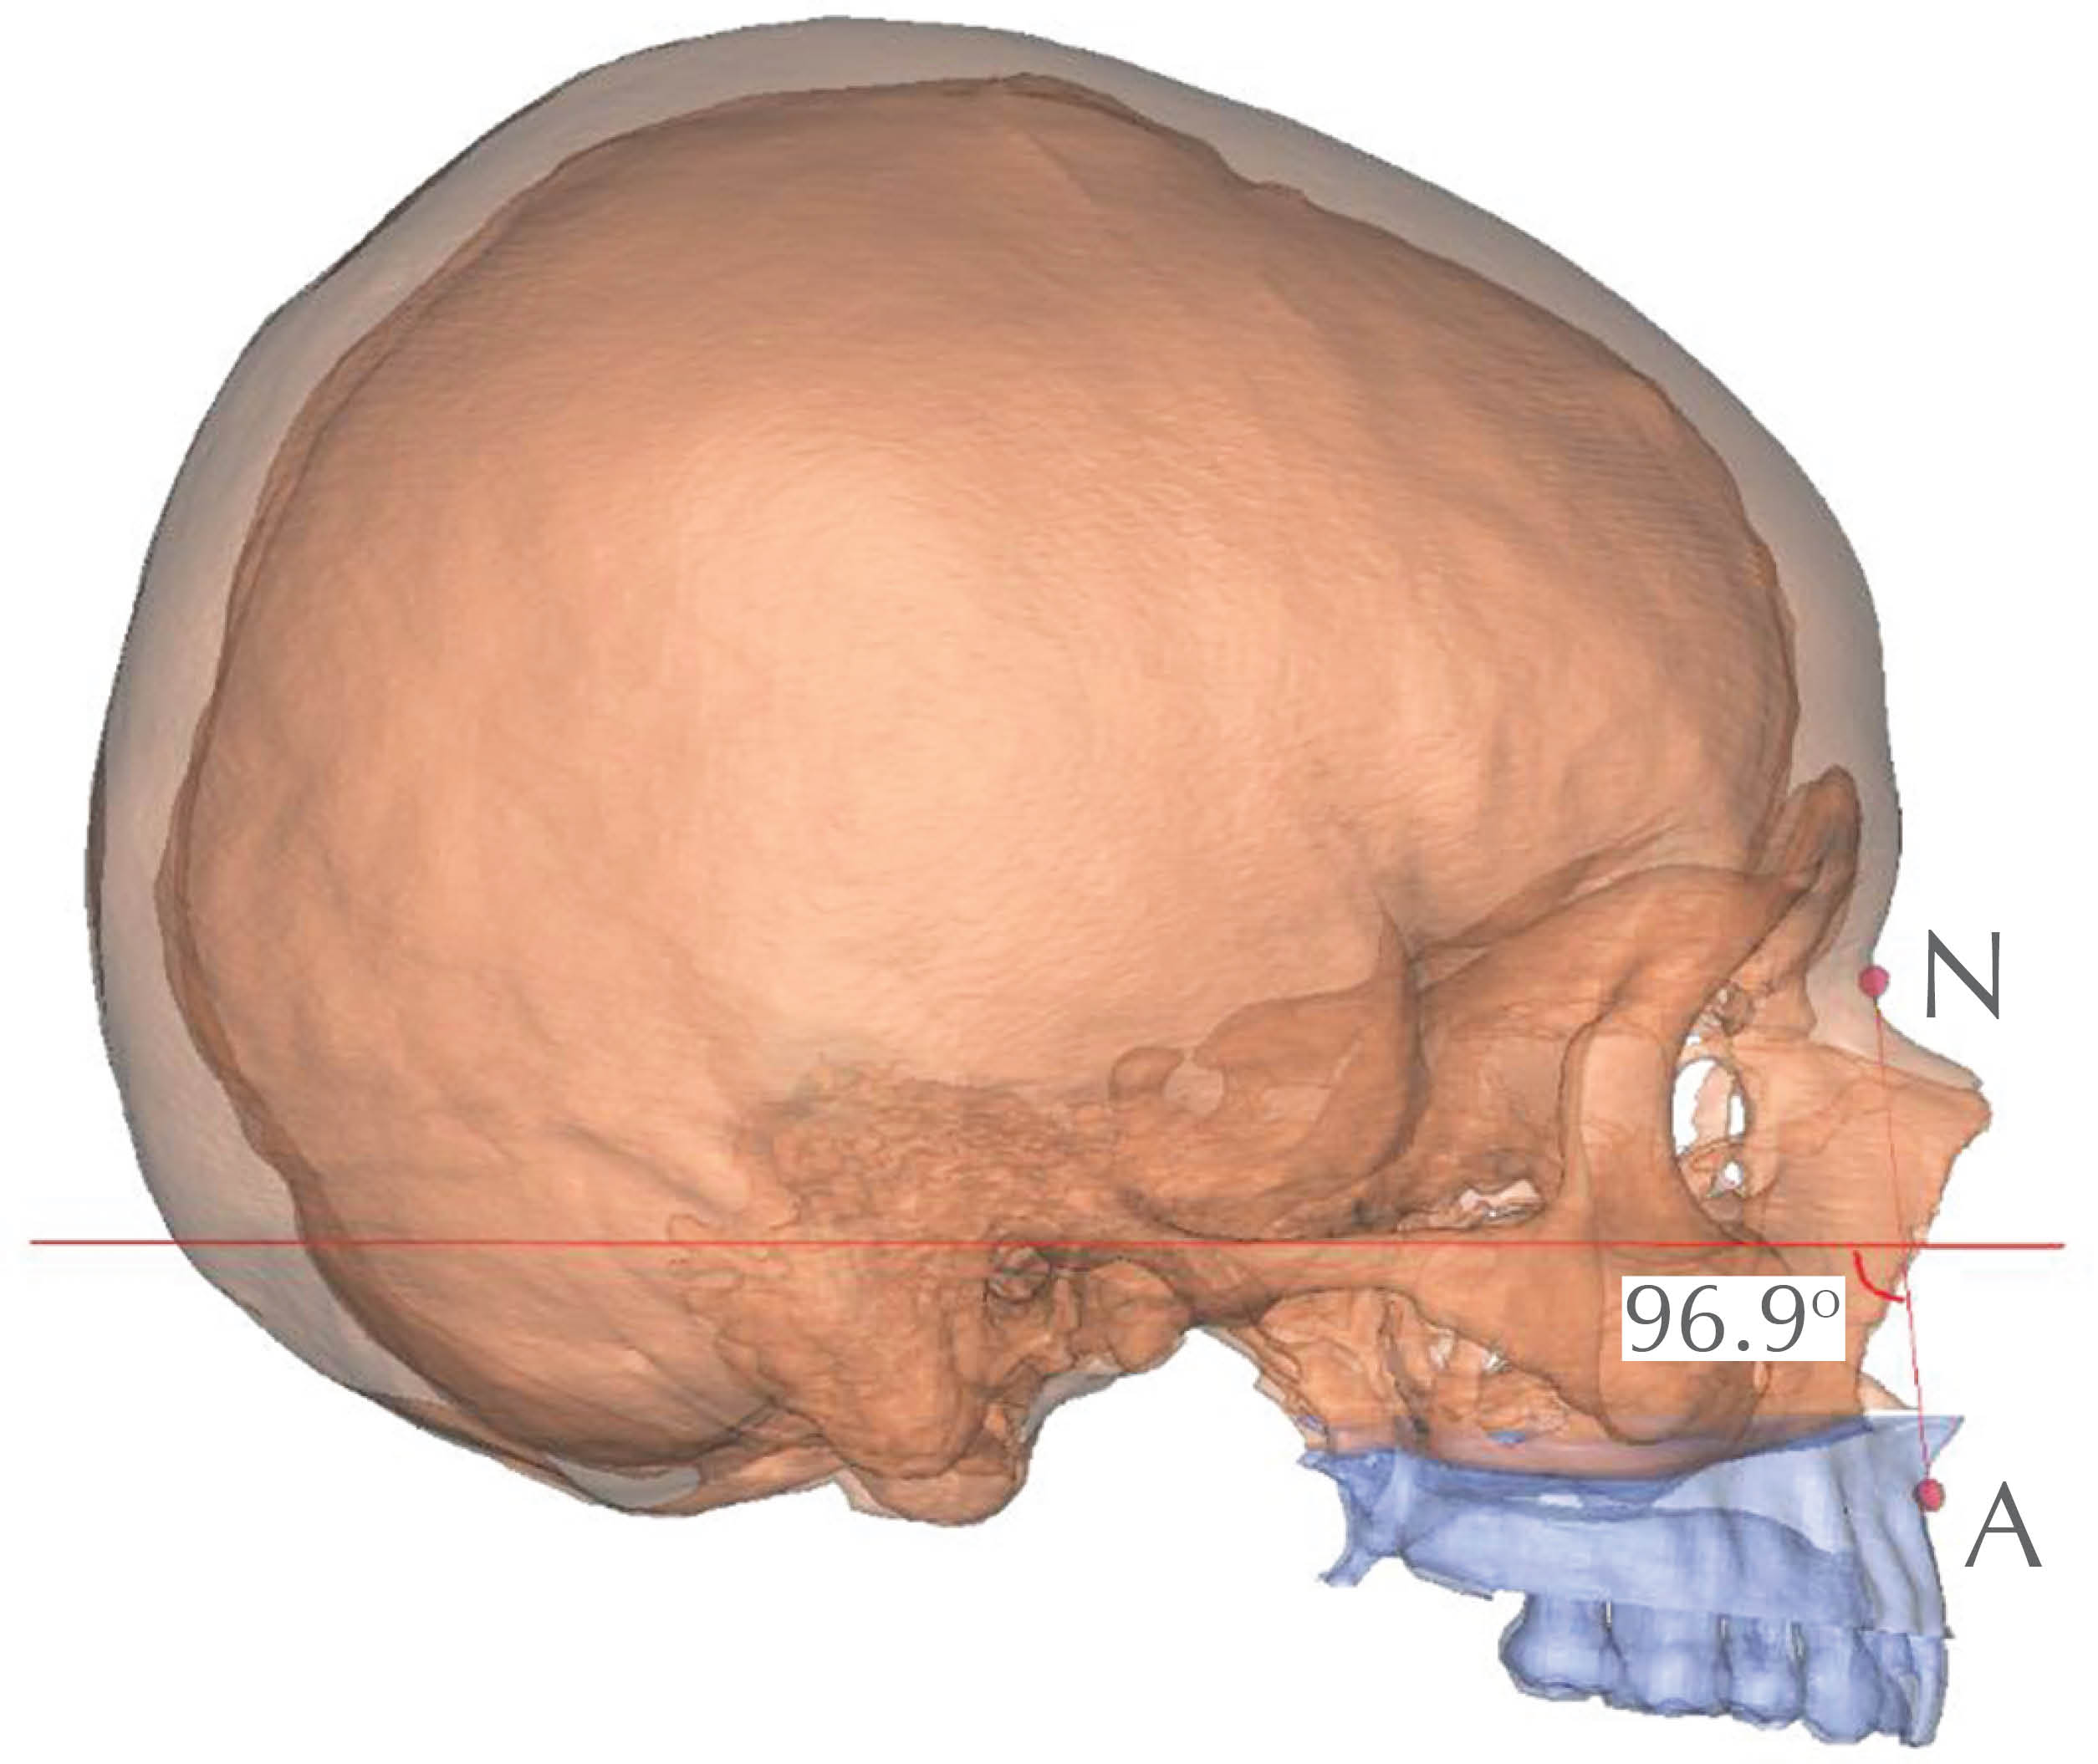

• 1. NA-FH: proyección del maxilar; es el ángulo formado por la intersección de las líneas nasión-punto "A" y el plano de Frankfurt o plano horizontal (Figura 9).

Figura 9